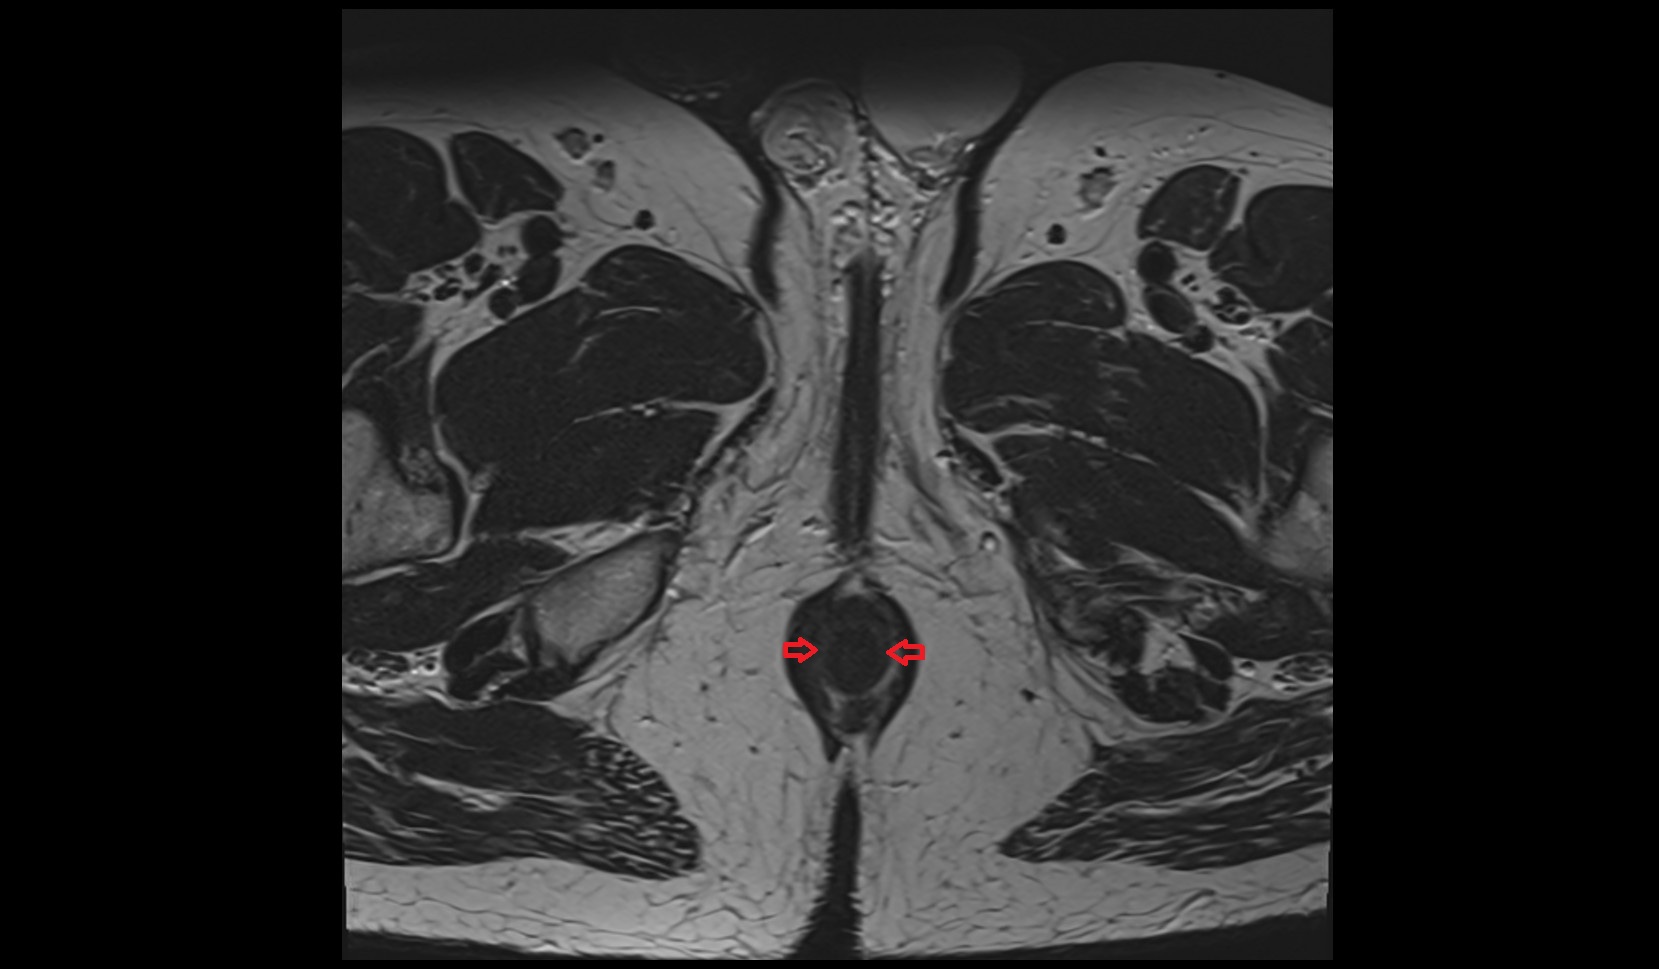

- Peripheral zone of prostate

- Anterior Fibromuscular Stroma of prostate

- Central zone of prostate

- Transitional zone of prostate